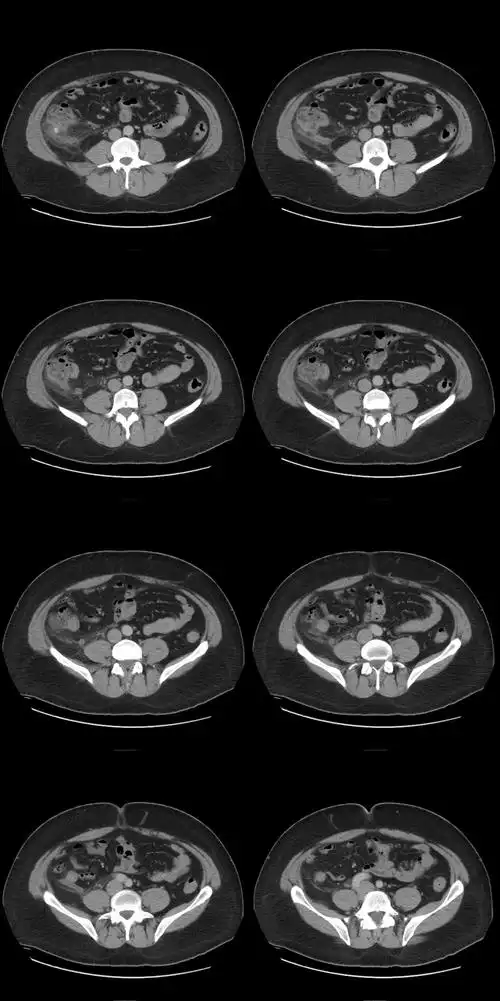

容易被误诊的右下腹疼痛之盲肠憩室炎